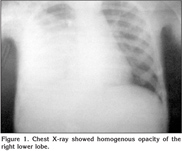

A 3-years six month old boy presented with fever since 15 days and cough since three days. There was no history of recurrent chest infections, hemoptysis, chest trauma, foreign body aspiration or chronic cough. On examination, he was febrile 103?F, RR 40/min, PR 106/min and BP 90/60 mmHg. He was sick, there was no cyanosis, clubbing or lymphadenopathy. His oxygen saturation was 92% in room air. His weight was 11 kg (< 5th percentile) and his height was 86 cm (< 5th percentile). Respiratory system examination revealed decreased movements on right side, diminished tactile fremitus with dullness on percussion at right infra scapular and axillary areas. Auscultation of the chest revealed decreased breath sound and decreased vocal resonance in the right infra scapular and axillary areas. Other systems examination was unremarkable. Clinically diagnosis of right pleural effusion/empyema was made. Investigations: -Hb 11.1 g/dL, Hct 34%, TLC 31.700/mm3, Neutrophils 74%, Lymphocytes 26%, platelets 700.000/mm3, ESR 60 mm, CRP 178 and blood culture was sterile. Chest X-ray showed homogenous opacity of the right lower lobe (Figure 1). Computed tomography (CT) scan of the chest showed multiple cysts with air fluid levels and one large cyst measuring 9 x 8 cm with multiple septations suggestive of infective CCAM with lung abscess. Pleural cavities are clear (Figure 2). She was started on inj ceftraiaxone and inj linezolid. The child underwent right thoracotomy and 70 mL thick pus was drained from the lung abscess and right lower lobectomy was done. Pus culture was sterile and negative for acid fast bacillus. He became afebrile after three days of lobectomy. He was given 14 days of antibiotics and discharged. Macroscopic examination revealed a lung lobe measuring 9.5 x 7.5 x 2 cm and cut section showed a large cystic cavity measuring 7.5 x 4 x 2 cm with a shaggy inner surface with surrounding yellow grayish areas. Microscopy of the lung showed many interconnected cysts lined by pseudostratified columnar epithelium with mucous secreting glands with abundant inflammatory cells suggestive of type-1 CCAM.

Figure 1